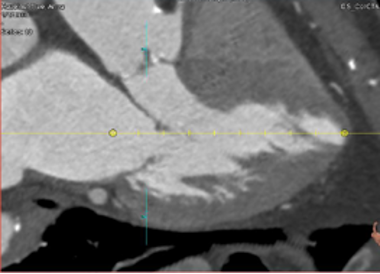

- Specific analysis services: Angiography (coronary and peripheral),Intravascular imaging (OCT- IVUS), QFR, iFR, MRI, Echocardiography (TTE, TEE), CT-scan (aortic & mitral valves, peripheric), Cardiac MRI, ECG and, aortography.

- Quantitative and qualitative assessments (Angiography, QCA, IVUS, OCT, QFR, ECHO, CT scan, MRI, ECG)

Cardiac CT-scan